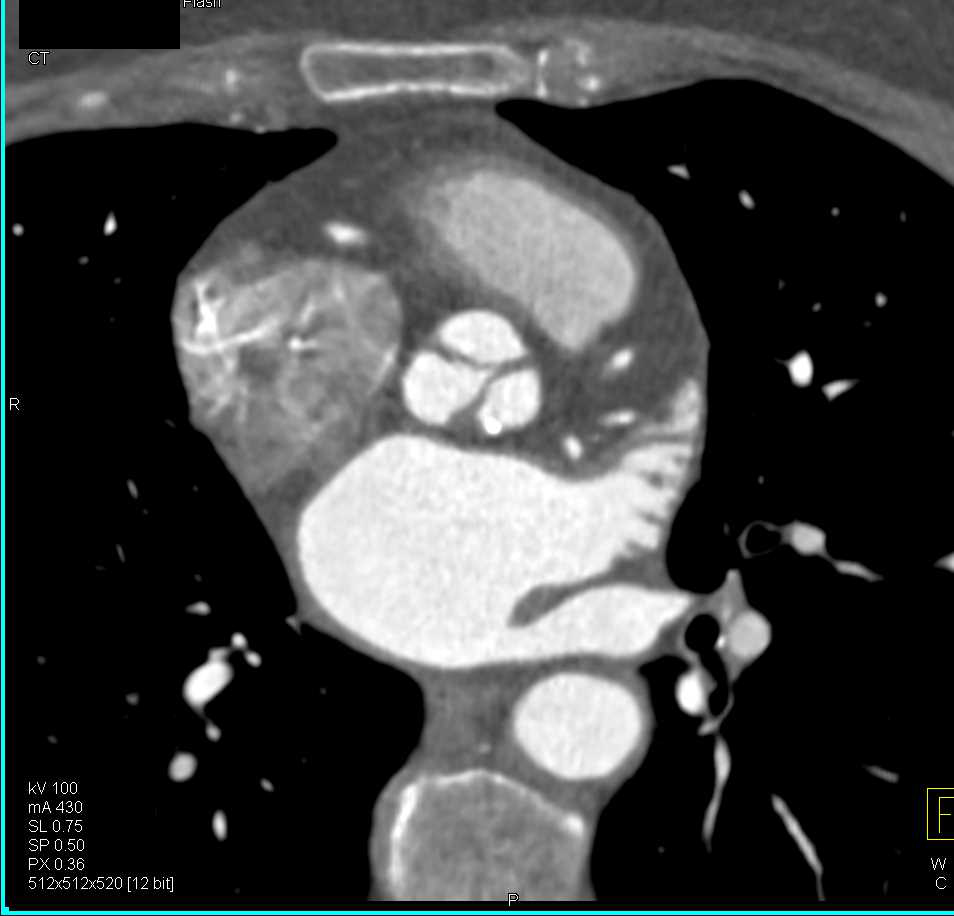

Endovascular Stent Repair of Thoracic Aorta